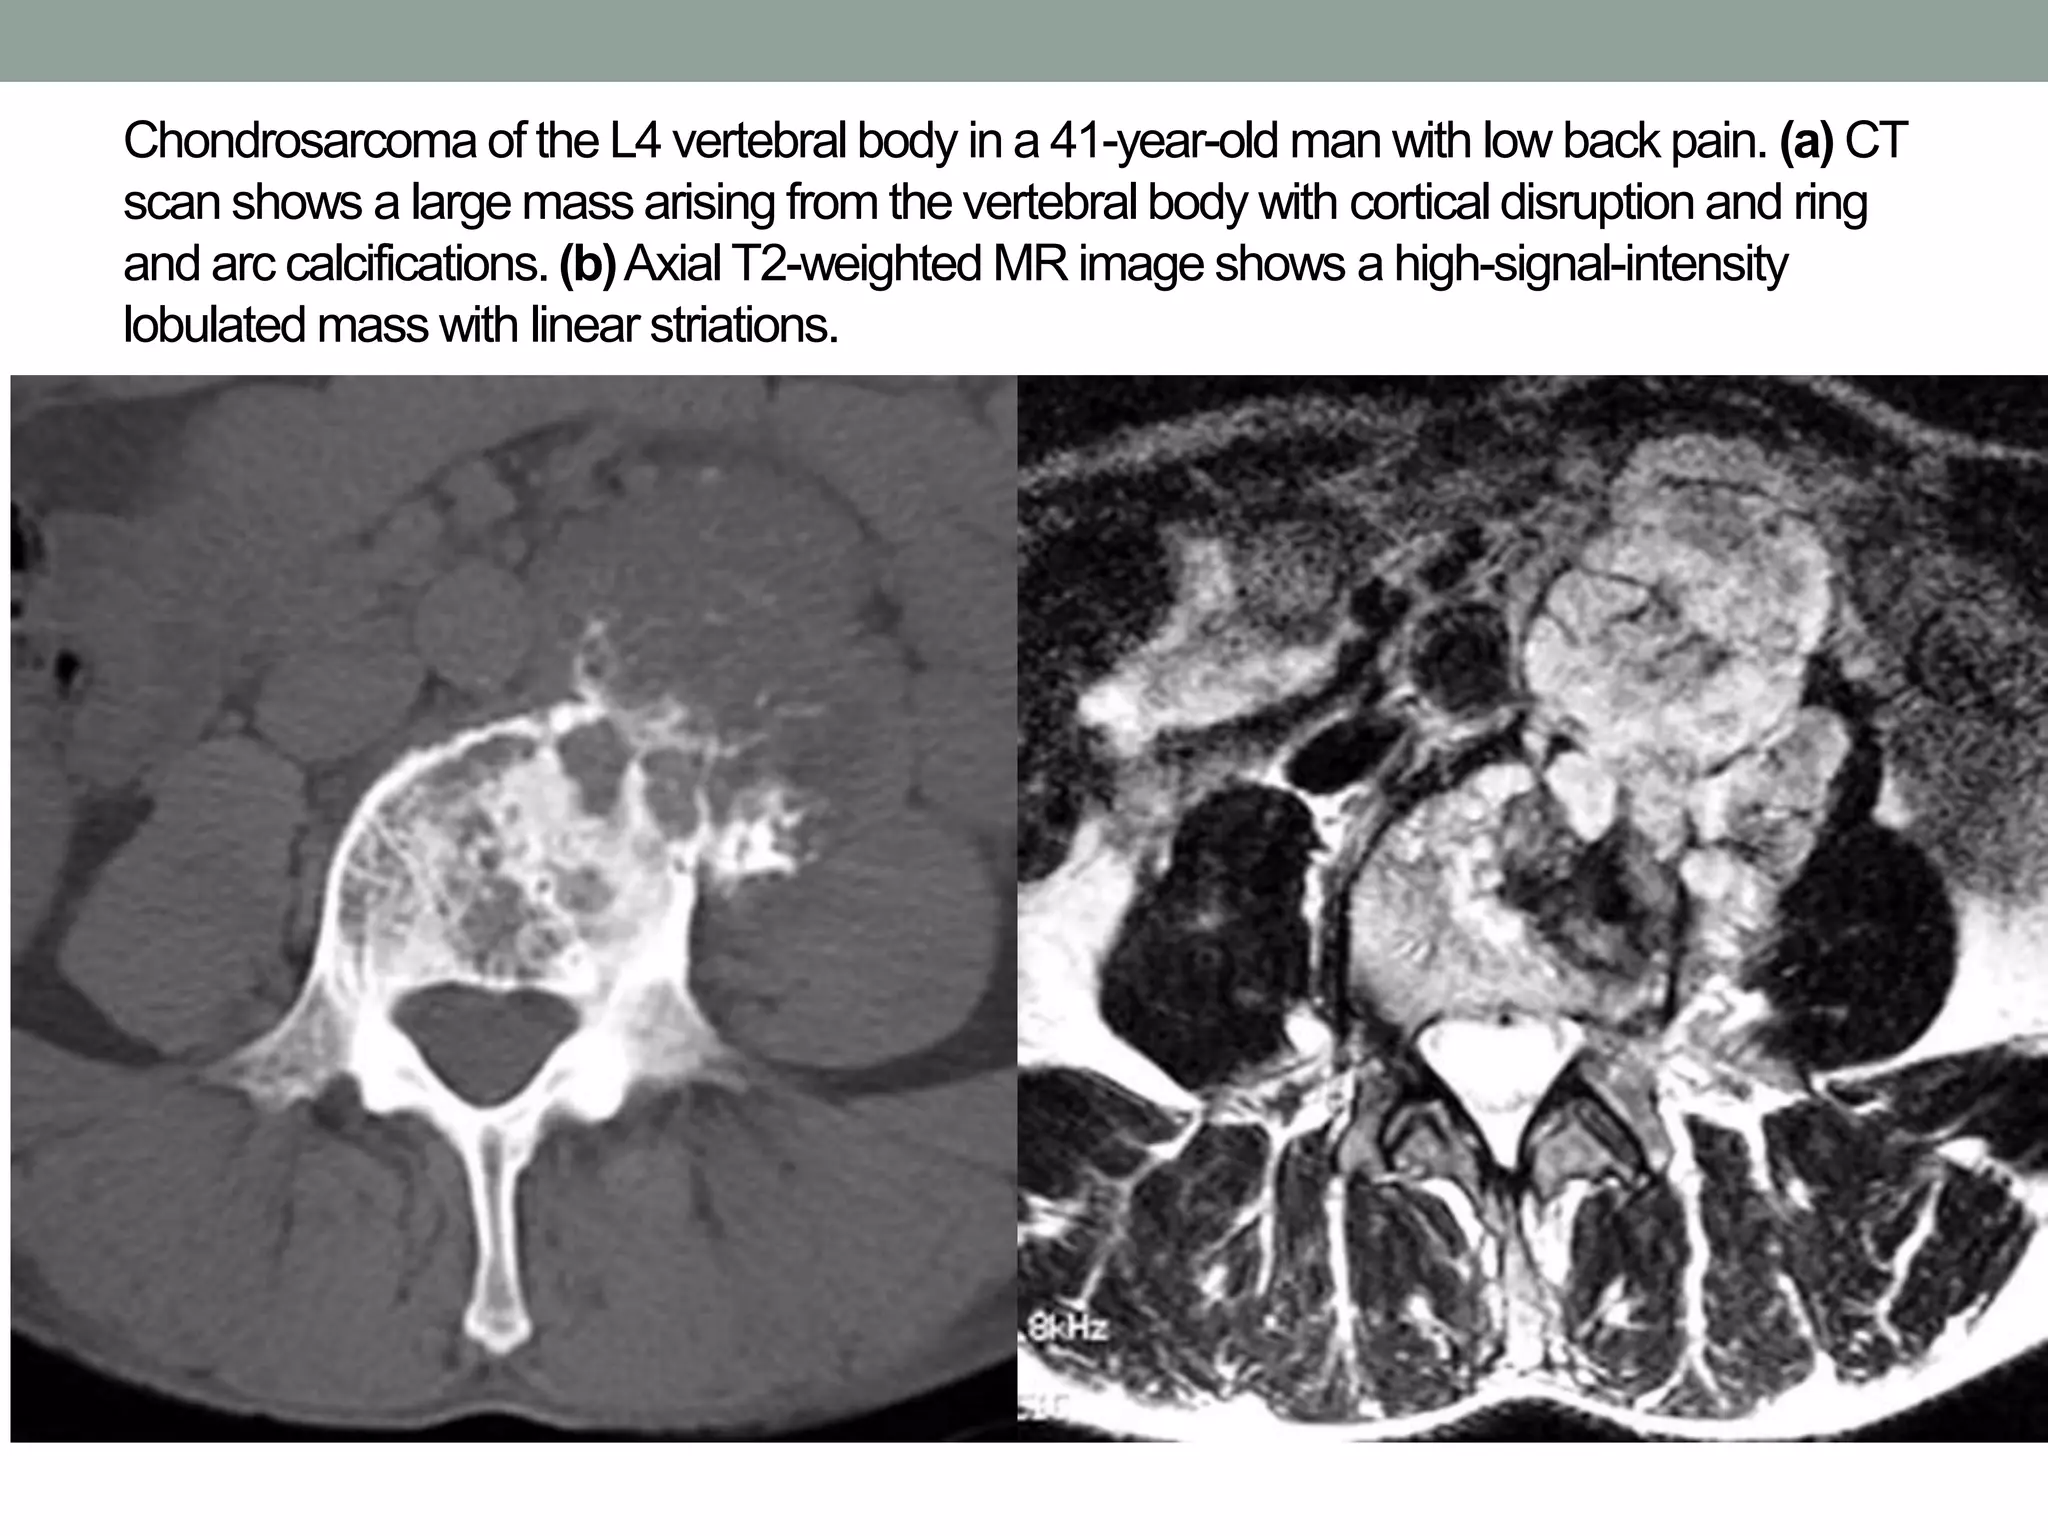

Chondrosarcoma of the L4 vertebral body in a 41-year-old man with low back pain. (a) CT

scan shows a large mass arising from the vertebral body with cortical disruption and ring

and arc calcifications.(b)Axial T2-weighted MR image shows a high-signal-intensity

lobulated mass with linear striations.